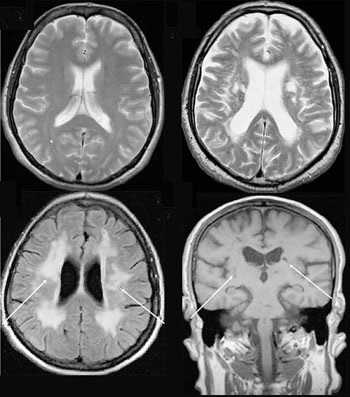

Что показывает МРТ

Магнитно-резонансная томография или МРТ - это сфокусированный метод, который проводит очень детальное обследование. Диагностическая точность МРТ превышает УЗИ и во многих случаях КТ, за исключением сканирования полых органов (легких, желудка, кишечника) и костей. МРТ является золотым стандартом диагностики:

- заболеваний головного и спинного мозга;

- патологий суставов;

- межпозвоночных дисков;

- сердца и сосудов;

- болезней гинекологического, проктологического и урологического характера.

Принцип работы МРТ основан на эффекте ядерного магнитного резонанса. МР томограф в своей конструкции имеет мощный магнит, который создает магнитное поле, и датчик, который подает радиочастотные сигналы. В такой ситуации протоны атомов водорода начинают колебательные движения, выделяя при этом импульсы. Их улавливает компьютер томографа и преобразовывает в трехмерные изображения. Чем больше воды содержится в клетках ткани, тем детальней получается ее изображение. Поэтому на МРТ хорошо отображаются органы с большим содержанием воды: МРТ головного мозга, МРТ спинного мозга, МРТ глазных орбит, МРТ органов малого таза, МРТ позвоночника, МРТ суставов, и плохо визуализируются органы с большим содержанием воздуха МРТ органов грудной клетки или кости.

Магнитно-резонансная томография

В основе МРТ лежит явление магнитного резонанса, основанного на переизлучении радиоволн, взаимодействующих с атомами водорода, в избытке содержащимися в организме человека. Эти переизлученные электромагнитные волны улавливаются датчиком МР-томографа, усиливаются и в виде цифровых изображений появляются на экране монитора. Это безвредный и абсолютно безопасный для здоровья человека метод лучевой диагностики, так как в основе получения изображения отсутствует рентгеновское излучение, поэтому МРТ можно проходить неограниченное количество раз, с любым интервалом.

Существенное преимущество МР-томографии перед КТ заключается в том, что она не противопоказана беременным во II и III триместре и совершенно безопасна для детей. В МРТ исследуемая область сканируется в трех проекциях, что позволяет врачу-рентгенологу в полной мере оценить состояние тканей и органов исследуемой области, а высокая контрастность изображения и пространственное разрешение позволяют визуализировать серое и белое вещество головного мозга, оценивать состояние костного мозга и мягких тканей различной локализации. Кроме того, метод МРТ позволяет получать изображения сосудов головного мозга и сосудов шеи без введения контрастного препарата.